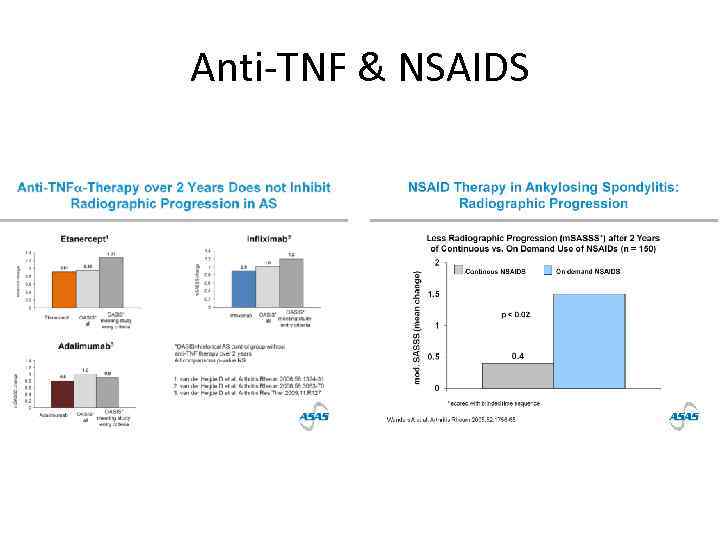

Anti-TNF & NSAIDS